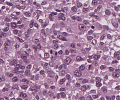

A52 Hodgkin-Lymphom

Mehrkernige Reed-Sternberg Zelle mit mit prominenten Nukleoli beim klassischen Hodgkin-Lymphom.